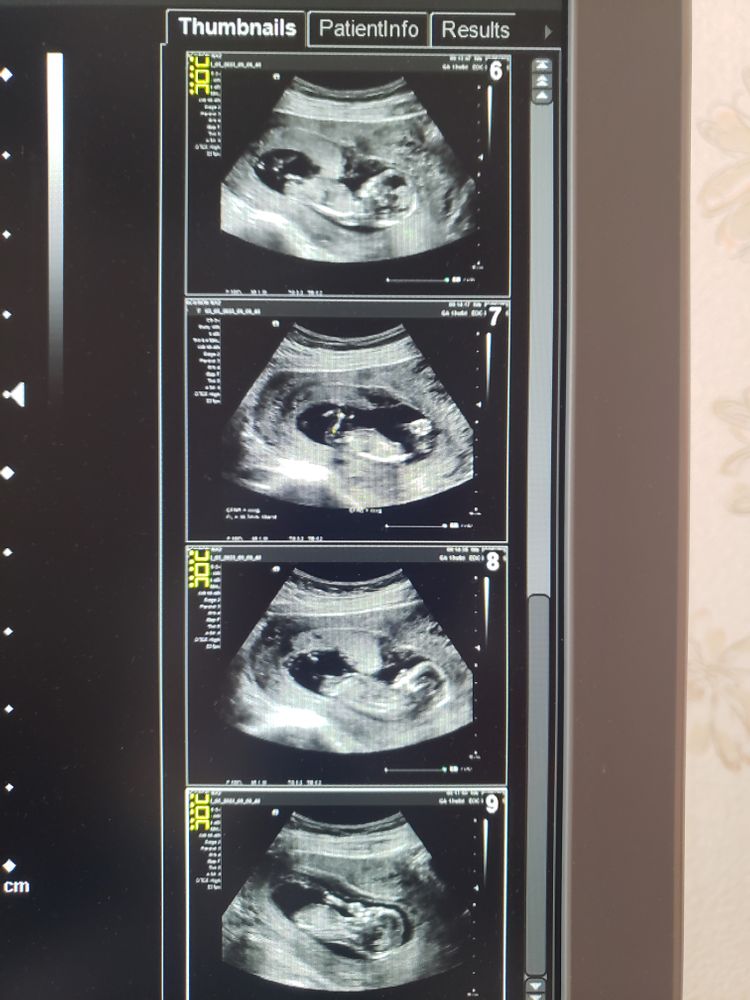

1й скрининг

Ну что жжжжж у нас будет маленькая Мия, как и мечтали🥰 муж узнал- расплакался 🥰🥰🥰🥰🤧срок по М 13 нед и 6 дней, по узи 13 нед и 3 дня. Все хорошо 🥰волшебные ручки, ножки, носик, губки, всёеее😍я счастлива. Сегодня , увидев ЕЕ уже такую большую, я полностью осознала, что скоро Мимишка будет с нами рядом !